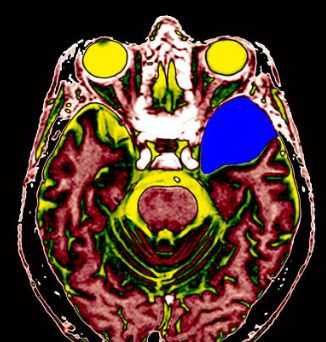

МРТ головного мозга. Т2-взвешенная аксиальная томограмма. Арахноидальная киста. Цветовая обработка изображения.

МРТ головного мозга. Арахноидальная киста полюса левой височной доли. Цветовая обработка.